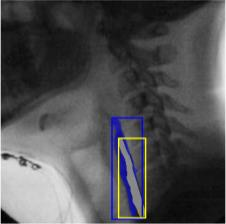

The videofluoroscopic swallowing study (VFSS) is a gold-standard imaging technique for assessing swallowing, but analysis and rating of VFSS recordings is time consuming and requires specialized training and expertise. Researchers have recently demonstrated that it is possible to automatically detect the pharyngeal phase of swallowing and to localize the bolus in VFSS recordings via computer vision, fostering the development of novel techniques for automatic VFSS analysis. However, training of algorithms to perform these tasks requires large amounts of annotated data that are seldom available. We demonstrate that the challenges of pharyngeal phase detection and bolus localization can be solved together using a single approach. We propose a deep-learning framework that jointly tackles pharyngeal phase detection and bolus localization in a weakly-supervised manner, requiring only the initial and final frames of the pharyngeal phase as ground truth annotations for the training. Our approach stems from the observation that bolus presence in the pharynx is the most prominent visual feature upon which to infer whether individual VFSS frames belong to the pharyngeal phase. We conducted extensive experiments with multiple convolutional neural networks (CNNs) on a dataset of 1245 bolus-level clips from 59 healthy subjects. We demonstrated that the pharyngeal phase can be detected with an F1-score higher than 0.9. Moreover, by processing the class activation maps of the CNNs, we were able to localize the bolus with promising results, obtaining correlations with ground truth trajectories higher than 0.9, without any manual annotations of bolus location used for training purposes. Once validated on a larger sample of participants with swallowing disorders, our framework will pave the way for the development of intelligent tools for VFSS analysis to support clinicians in swallowing assessment.